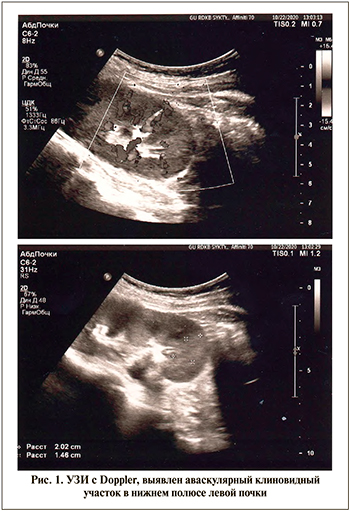

С учетом сохраняющихся у пациентки субфебрилитета и клинико-лабораторных провоспалительных изменений проведена КТ грудной клетки и органов брюшной полости (рис. 2). На томограммах органов грудной клетки признаков очаговой и инфильтративной патологии легких, органов средостения не выявлено. Состояние костных структур позвоночника соответствует перенесенной корригирующей операции. После контрастного усиления в венозную фазу в нижнем полюсе левой почки обнаружен участок сниженного контрастирования клиновидной формы размером 20×17×29 мм (рис. 3). Не выявлено деформации контура почки и изменений в прилежащей паранефральной клетчатке, накопления контраста в паренхиме почки на границе образования, которое имеет однородную структуру. Перечисленные рентгенологические особенности образования и его клиновидная форма позволили исключить абсцесс почки и считать выявленные признаки следствием острого нарушения кровоснабжения в нижнем полюсе левой почки, диагностировав инфаркт левой почки.